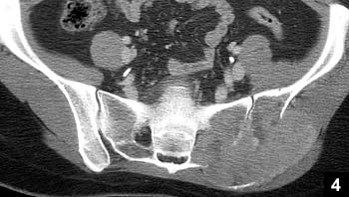

14歳男性:下肢の筋力低下

• CT

• T2WI

• T1WI

• Gd-T1WI